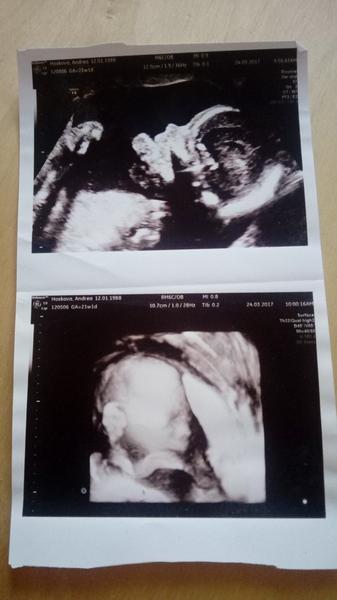

Dobrý den mám dotaz jsem objednaná na ultrazvuk do porodnice k Apolináři. Chci se optat platí se vyšetření? Na krvi jsem už byla za 2 týdny jdu na ultrazvuk tak mě zajímá jestli si mám dát penízky stranou a zda mi tam udělají fotku miminka děkuji moc za informaci

Byl to pekny zazitek. My jsme se ji asi libili nejak vic,vytiskla nam i 3d fotku a obyc,ale platili js jen za tu obyc. Byla jsem asi ve 22tt

Ja byl v 13 týdnu, byly fakt moc milé. Nám výtisky taky 2 fotecky. Nám paní doktorka rekla ze nemaji 3D ultrazvuk